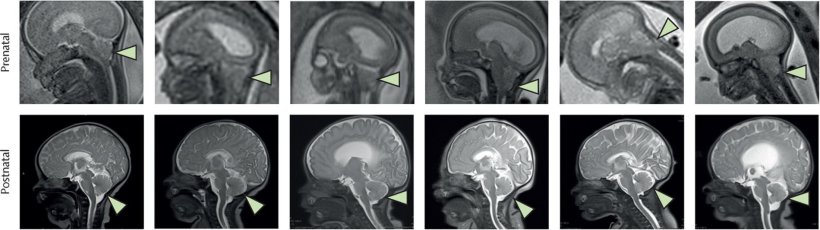

All six babies, who were born between July 2021 and December 2022, had their spinal repairs intact and showed no signs of infection, abnormal tissue growth, or tumour formation. Post-birth MRI scans confirmed that brain abnormalities associated with spina bifida, called hindbrain herniation, were reversed in every case.